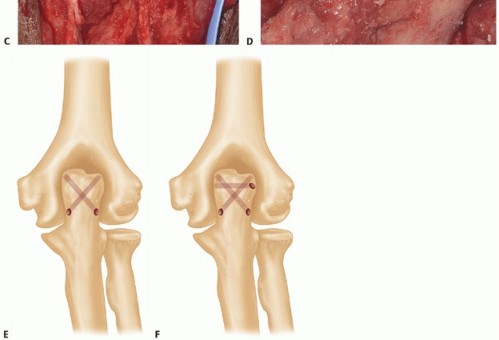

The triceps tendon should be reattached to the flat of the olecranon process, not to the tip (TECH FIG 6C,D). Pass the sutures through bone tunnels (oblique crossing) that begin on the periphery of the flat reattachment area of the olecranon (TECH FIG 6E).

TECH FIG 6 • (continued) C,D. The triceps footprint to which reattachment should be attempted is predominantly on the flat part of the ulna or olecranon process, and not the tip, which is resected to prevent posterior abutment. E. Drill holes (1.5 to 2 mm) are oriented in a crossing fashion to secure the triceps to the footprint area. F. A separate cinch suture is used to increase the security and the area of contact between the triceps and the ulna, thereby improving healing potential.